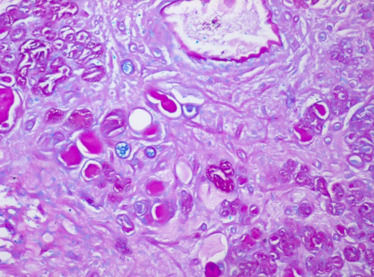

O estudo anatomopatológico revelou tratar‐se de uma lesão epitelial constituída por estruturas tubuloglandulares revestidas por células cuboides de citoplasma claro, com infiltrado inflamatório linfoplasmocitário e edema do estroma associados (fig. 1 ). Não se identificaram nucléolos, mitoses, necrose nem desmoplasia. Algumas estruturas continham mucinas neutras (PAS  +) e mucinas ácidas (Alcian Blue +) intraluminais (fig. 2 ). O estudo imunohistoquímico mostrou expressão de citoqueratina 7 (fig. 3 ), P504s (alfa‐methylacyl coenzime A racemase [AMARC]) (fig. 4 ) e índice proliferativo (Ki67/mib1) baixo, inferior a 2%. Para o diagnóstico diferencial foram também estudados outros anticorpos: citoqueratina 20, p53, p63, CA125 e CEA, que foram negativos. Pelas características morfológicas e imunohistoquímicas, foi realizado o diagnóstico de adenoma nefrogénico da bexiga.

Estruturas tubuloglandulares revestidas por células cuboides de citoplasma claro ...

Figura 1.

Estruturas tubuloglandulares revestidas por células cuboides de citoplasma claro (setas), com infiltrado inflamatório linfoplasmocitário e edema do estroma associados (Hematoxina/Eosina; 200 x).